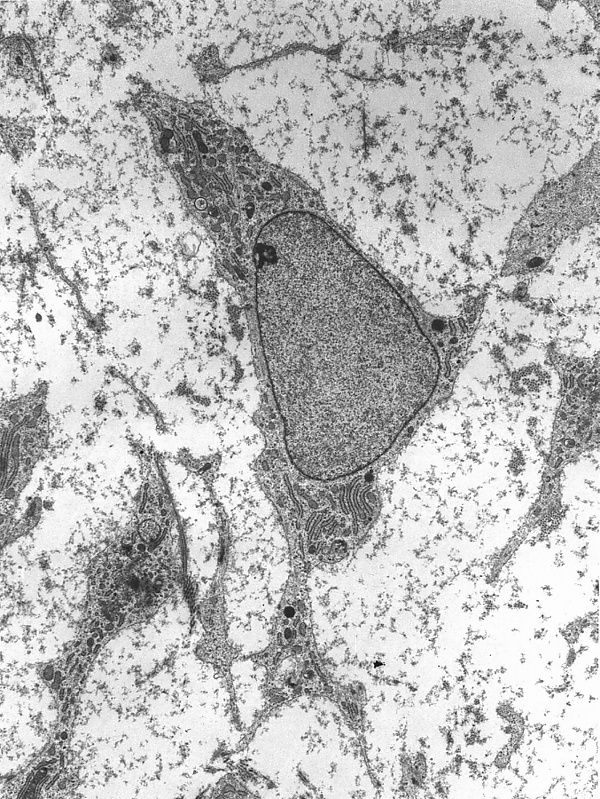

Стволовы́е кле́тки — недифференцированные (незрелые) клетки, имеющиеся у многих видов многоклеточных организмов. Стволовые клетки способны самообновляться, образуя новые стволовые клетки, делиться посредством митоза и дифференцироваться в специализированные клетки, то есть превращаться в клетки различных органов и тканей.

Стволовые клетки можно разделить на три основные группы в зависимости от источника их получения: эмбриональные, фетальные и постнатальные (стволовые клетки взрослого организма).

Эмбриональные стволовые клетки (ЭСК) образуют внутреннюю клеточную массу (ВКМ), или эмбриобласт, на ранней стадии развития эмбриона. Они являются плюрипотентными.